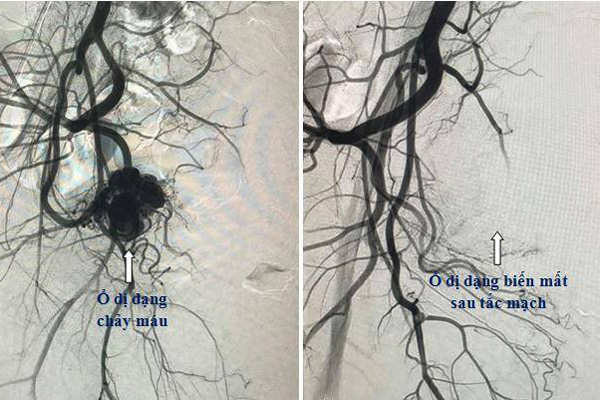

| Hình ảnh búi dị dạng gây chảy máu trong động mạch tử cung của bệnh nhân |

Người bệnh đã được chụp cắt lớp vi tính để chẩn đoán nguồn gốc gây chảy máu, phát hiện dị dạng, giả phình động mạch tử cung, đây là nguyên nhân gây vỡ và làm chảy máu liên tục, gây mất máu cho người bệnh.

Theo BS Lục, với các trường hợp như chị Ngân, phương pháp điều trị là phẫu thuật thắt động mạch hoặc cắt bỏ tử cung thì hiện nay, với nền y học hiện đại, kỹ thuật can thiệp mạch được ứng dụng và là lựa chọn đầu tiên và hiệu quả nhất.

Theo đó, bác sĩ dùng ống thông và dây dẫn tiếp cận với vị trí dị dạng mạch để nút ổ dị dạng bằng các vật liệu gây tắc mạch. Thời gian thực hiện phẫu thuật chỉ mất 30 phút đến 1 giờ. Đây cũng là thuật can thiệp ít xâm lấn nên bệnh nhân không phải nằm viện lâu.